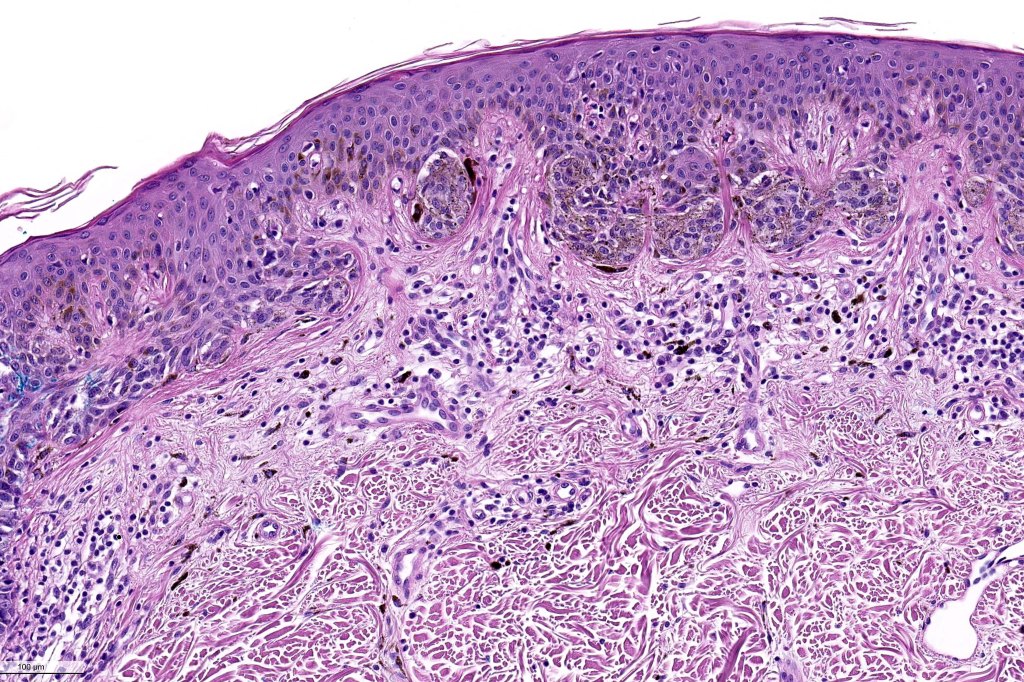

Histological features

•Architectural disorder- lentiginous and nested, nests abnormally located (at the sides of the rete ridges & overlying the dermal papillae in addition to the tips of the rete ridges rather than solely occupying the tips of the rete ridges as is seen in banal nevi), horizontal orientation & bridging between junctional nests (this should not be confused with bridging between adjacent rete ridge squamous epithelium)

•Abnormal fine pigmentation (dusty)

•Host response- eosinophilic & lamellar fibroplasia, increased vascularity, lymphocytic infiltration & pigment incontinence